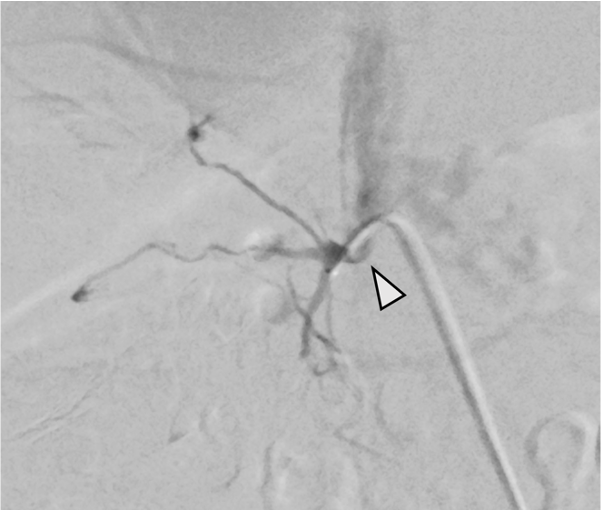

当該疾患の診断における造影CTの役割

原発性アルドステロン症は, 治癒可能な二次性高血圧であり, 本態性高血圧より脳・心血管, 腎合併症の頻度が高く, その診断および治療の重要性が指摘されている, 片側性のアルドステロン症の場合, 外科的切除によりアルドステロン過剰の正常化, 高血圧および臓器障害の改善・防止が期待できる, このため, 手術が考慮される場合には副腎静脈サンプリングによる機能的局在診断を行う, 原発性アルドステロン症診療ガイドライン20211)では, この副腎静脈サンプリングの成功率を向上させる方法の一つとして, ダイナミックmulti-detector row CT(MDCT)が推奨されている, MDCTでは, 横断像やMPR(Multi planar Reconstruction)を用いて, 副腎静脈の走行やvariationの確認などを行うが, これに加え当院では,仮想透視画像を作成し, 右副腎静脈の下大静脈開口部のレベルや, 副肝静脈との位置関係など, 立体的な解剖学的把握を行っている, その結果, サンプリング時に, スムーズかつ的確なカテーテル操作が可能となる.

本検査における後期動脈相は, 右副腎静脈と下大静脈との合流部, また左副腎静脈と下横隔静脈, 腎静脈との合流部の形態評価が求められる重要な撮影時相である. そのため30sec注入時間固定法とbolus tracking法の併用を行い, 腹部下行大動脈において+100HUのCT値上昇をトリガーとし, 20secのdelay timeにて後期動脈相の撮影を行っている. その後の門脈優位相は, トリガーから40secの撮影とし, 主に副肝静脈と下大静脈との合流部の形態評価が目的とされる. 造影コントラスト向上のため. 可能な限り低管電圧撮影が行えるよう留意している. なお, 本症例は, 造影剤量がプロトコルより少ない症例であったが, 低管電圧撮影や後期動脈相の最適な撮影タイミングにより, 副腎静脈を良好に描出し得た.